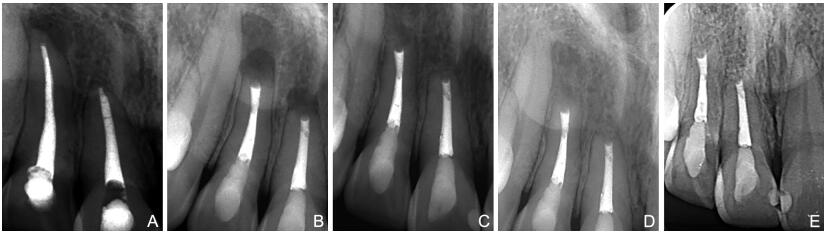

iRoot BP Plus和MTA作为根尖倒充填材料在显微根尖手术应用中的近期临床疗效观察

王璐, 吴光远, 李午丽

2023, 21(4): 585-588. doi: 10.16766/j.cnki.issn.1674-4152.002936

摘要:

目的  根尖倒充填是显微根尖手术的关键步骤之一,倒充填材料的选择影响手术的预后,本研究旨在评估新型生物陶瓷材料iRoot BP Plus作为根尖倒充填材料在显微根尖手术应用中的近期临床疗效并与三氧化物聚合物(MTA)相比较,以期为临床倒充填材料的选择提供参考。  方法  选取2018年12月—2020年12月在安徽省口腔医院牙体牙髓儿童牙病科诊断为慢性根尖周炎需要进行显微根尖手术的患者60例(81颗患牙),在取得患者知情同意后, 按照随机数表分为2组,试验组为iRoot BP Plus组29例(39颗患牙), 对照组为MTA组31例(42颗患牙),由同一术者按标准化步骤对患者实施显微根尖手术。术后3个月、6个月、1年随访, 1年随访时获得的临床和X线评估资料作为疗效评定的主要依据, 对2组临床疗效进行评定, 并对2组成功率和预后影响因素进行统计学分析。  结果  iRoot BP Plus组患者的成功率为92.3%,MTA组为90.5%,差异无统计学意义(P>0.05);影响显微根尖手术疗效的相关因素分析结果显示患者性别、年龄以及牙位之间的比较差异无统计学意义(均P>0.05),尽管病变直径≤10 mm的1年随访成功率较病变直径>10 mm高(95.1% vs. 80.0%), 但差异无统计学意义(χ2=2.639,P=0.104)。  结论  本研究初步证实了iRoot BP Plus和MTA作为根尖倒充填材料均能取得满意的效果,值得临床推广应用。